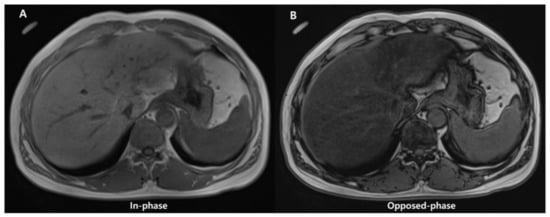

Conventional qualitative methods, including chemical shift image (Figure 6) or fat-suppression techniques (T1-weighted gradient-echo and T2-weighted fast spin-echo sequences), have been used for qualitative evaluation of steatosis. However, they are unsuitable for quantitative evaluation due to multiple confounding variables that reduce their accuracy (discussed later).

Figure 6.

Images of in- (A) and opposed-phase (B) of chemical shift MRI. In (B), the liver parenchymal signal is lower compared with (A) due to signal drop caused by hepatic fat deposition.